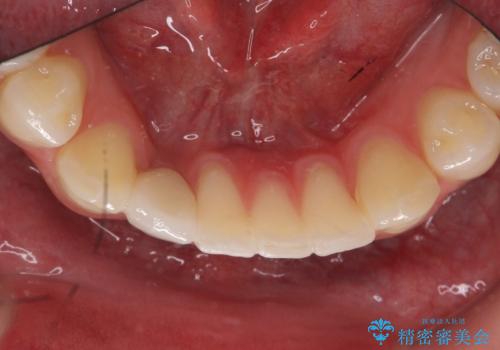

被せ物の色を決める前に、ホワイトニングを行なっています。

- 45万円(税別) 内訳:ストローマンインプラント(1本)20万円、ジルコニアクラウン10万円、シリンダーTeC 2万円 ジルコニアカスタムアバットメント10万円 ホワイトニング(エクセレント)3万円費用は治療当時の料金となります

唇側の骨増成もしっかり行い、前歯部インプラントによくある、歯茎が下がって見えることもない、審美的なインプラント補綴ができました。